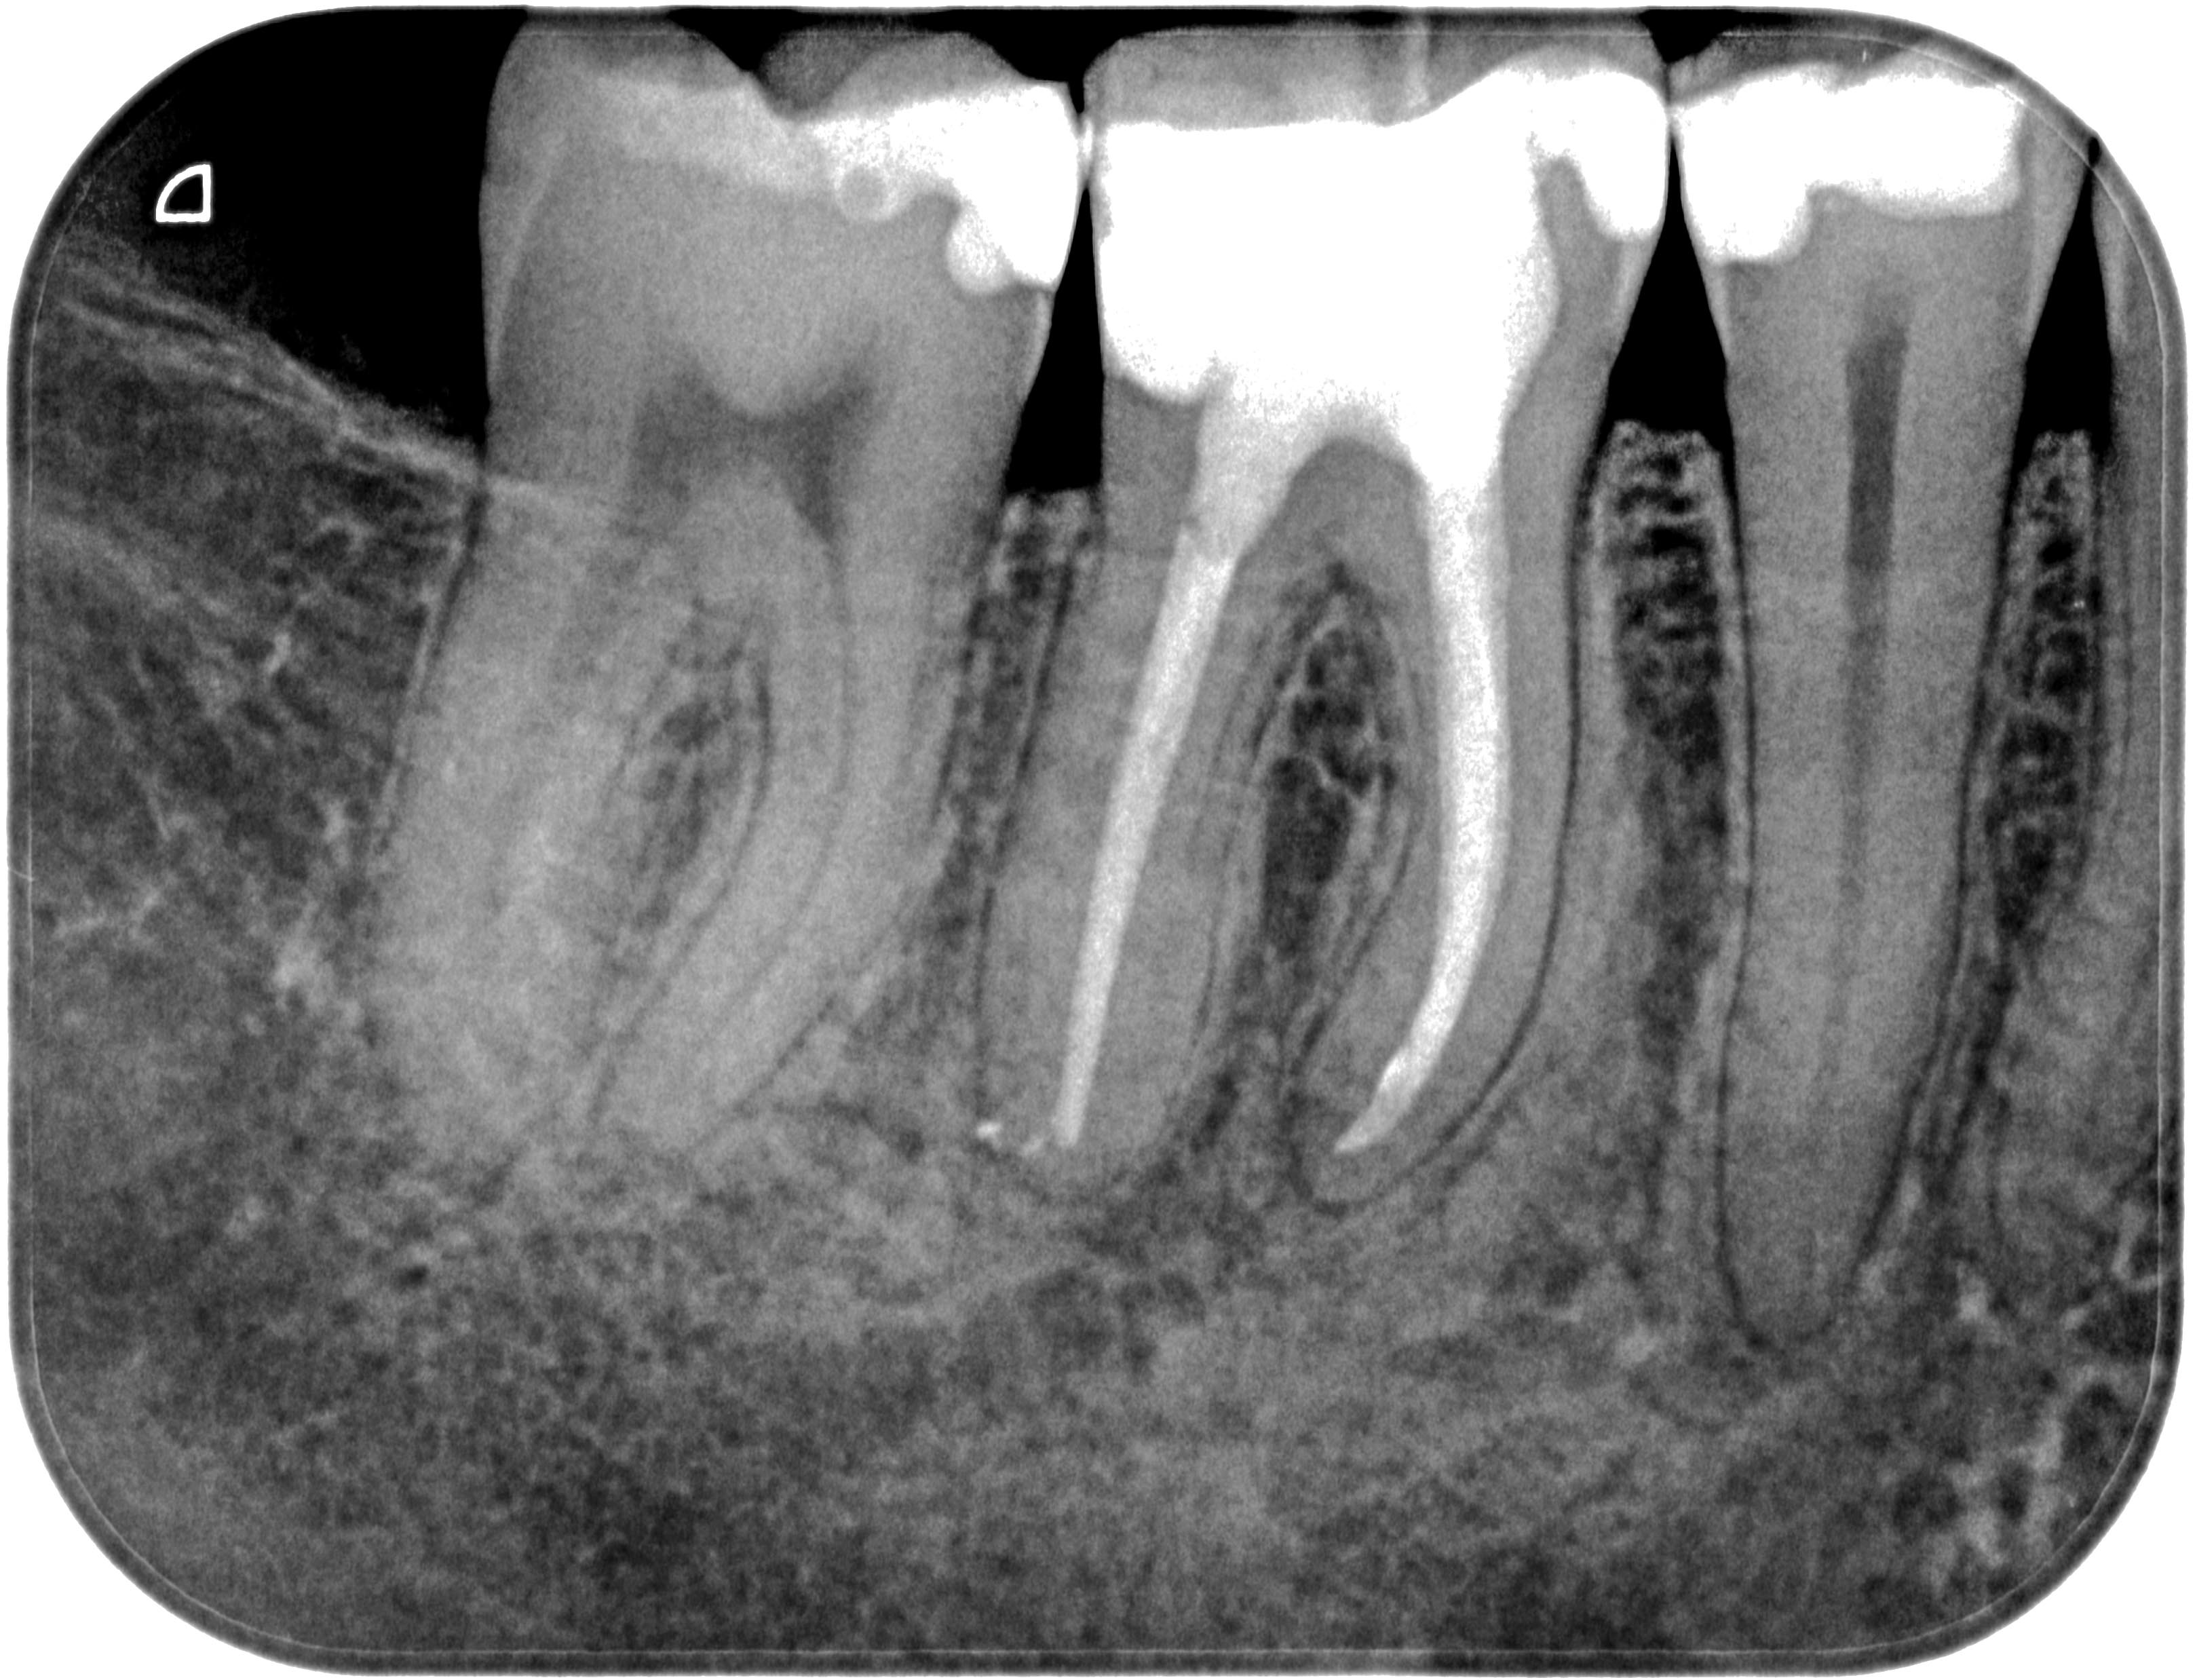

WS46 (1 von 1)-2 Veröffentlicht 21. März 2016 am 3238 × 2476 in Calciumhydroxid- Überpressung (2) 18. September 2013